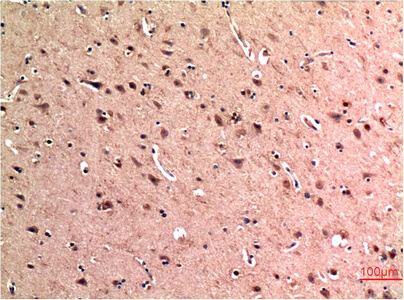

What makes the Abbkine Beclin-1 5C2 Monoclonal Antibody (ABM0079) stand out in a sea of options? It’s the “works everywhere” vibe. Western blots? It picks up endogenous Beclin-1 at ~60 kDa in starved HeLa cells (EBSS-treated) with a crisp band, even after 12% SDS-PAGE. Immunofluorescence? Stain autophagosomes in U2OS cells co-transfected with GFP-LC3, and the 5C2 signal overlaps perfectly with puncta—no more guessing if you’re looking at Beclin-1 or background. IHC on FFPE liver sections from NASH models? It localizes Beclin-1 in hepatocytes without the high background that plagues older clones. Abbkine’s not shy about sharing the data either: raw blot images, IF colocalization stats, and IHC scoring rubrics are all on their site. Transparency like that? Rare.